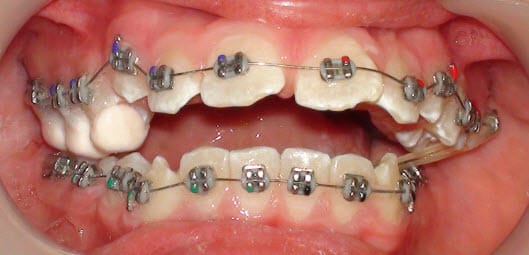

Pas d’affolement, commence par une traction sur élastiques croisés avec surélévations en CIV de l'autre coté et il y a de fortes chances que ta "micromandibulie" se corrigera toute seule. C'est un cas relativement classique.

Voici un exemple. Cela peut paraître gênant mais c'est beaucoup moins encombrant qu'un berlingot..

Daniel

Il faut déjà levée la supraclusion pour libérer la mandibule, tu peux le faire avec un multibague puis une fois la supra lévée, tu peux utiliser un propulseur mandibulaire de type PUL (cela marche très bien) et il est bien tolérée.

Mais dans ce cas il ne s'agit pas d'une vraie supraclusio! C'est une infralaterale mandibulaire, donc il ne faut surtout pas ingresser le haut mais plutot egresser les secteurs lateraux mandibulaires! Le plan occlusal maxillaire est presque droit, mais le plan occlusal mandibulaire presente une marche d'escalier terrible (entre le bloc incisivo-canin et les dents posterieures).

--

Said